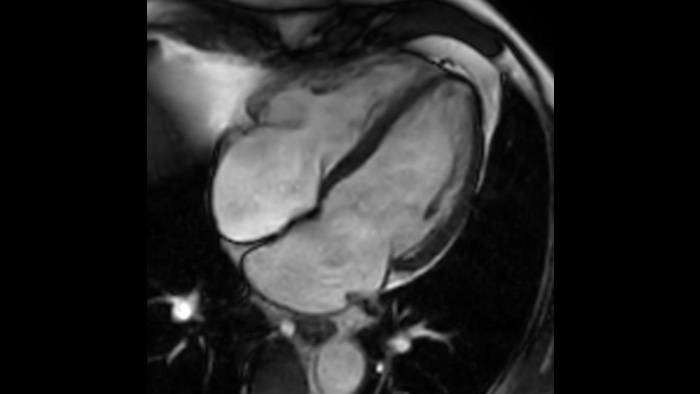

Szybkość Wykonuj nawet o 50% szybsze badania MR2, aby mądrze zarządzać czasem.

Komfort pacjenta Zapewnia do 40% redukcji wstrzymań oddechu przy praktycznie równej jakości obrazu.3

Pewność diagnostyki Zapewnia do 60% wyższą rozdzielczość przestrzenną przy takim samym czasie skanowania.4

Szybkość Przyspiesz pełne badanie nawet o 50% przy praktycznie takiej samej jakości obrazu.2

Pewność diagnostyczna Poszerz swoje możliwości obrazowania we wszystkich obszarach klinicznych. Zobacz, jakie korzyści odnoszą inni przedstawiciele Twojej branży.